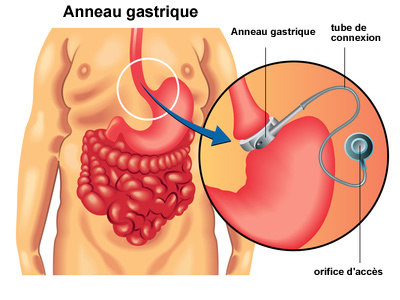

Gastroenterology is the branch of medicine which mainly deals with the sicknesses of the esophagus, stomach, small intestine, colon and rectum, pancreas, gallbladder, bile ducts and liver.

Bariatrics is the branch of medical that deals with the causes, prevention, and treatment of obesity. Bariatric surgery is an activity that is performed with a specific end goal to enable such people to lose weight. Evidence recommends that bariatric surgery may bring down death rates for patients with serious weight, particularly when combined with adhering to a good diet and way of lifestyle after surgery.